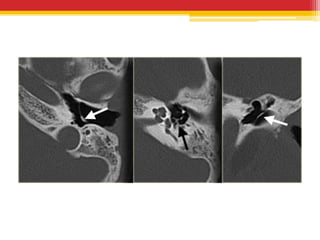

• CT temporal bones – USUALLY NOT

INDICATED, reveals unifocal or multifocal

masses or linear calcific densities in middle ear ,

epitympanum or in the tympanic membrane.